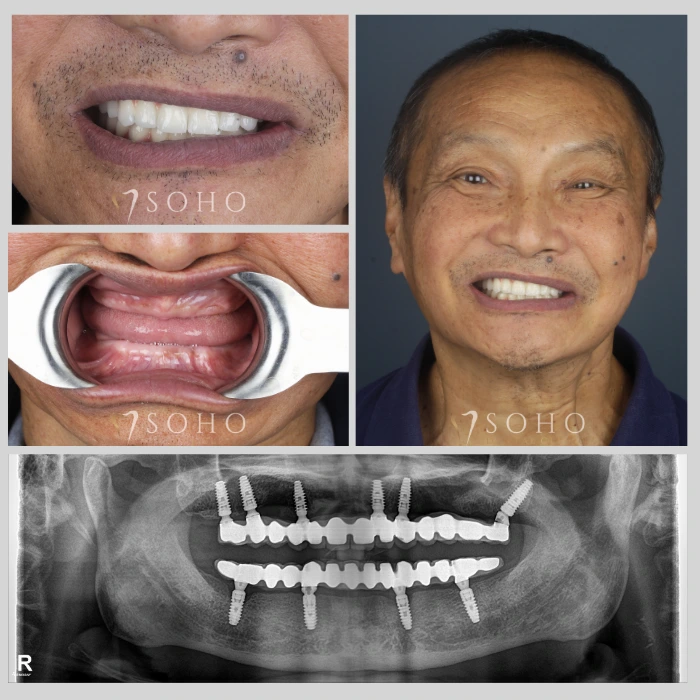

Dental Implants

Real Patients. Real Smiles.

Explore the journey of our international patients through authentic visuals, elegant transformations, and moments captured inside Soho Dental Clinic. Let their stories inspire your own.

From First Visit to Final Smile.

Explore real patient stories captured in every transformation. These are more than smiles — they are renewed confidence, achieved with care and precision at Soho Dental Clinic.